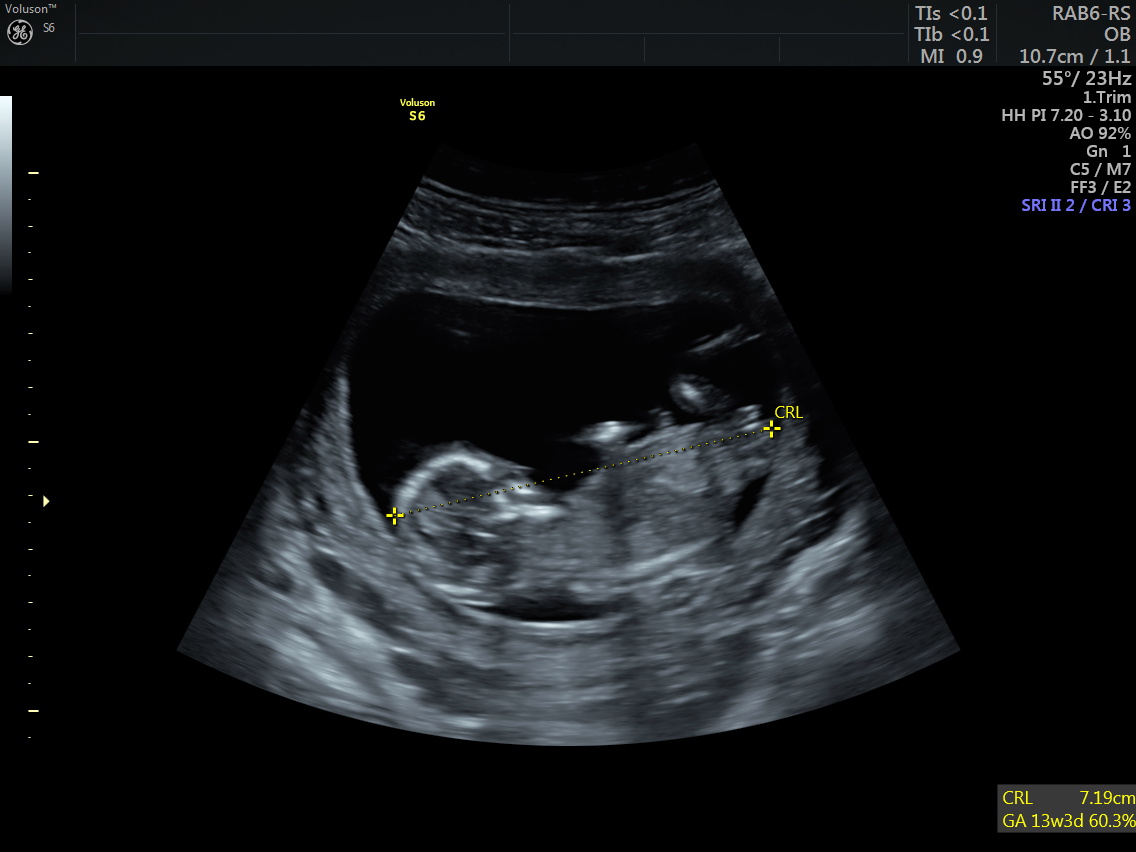

Benim bebeğime de bakar mısınız 12 hafta 3 günlük

cinsiyet tahmini yapar mısınız?

Merhaba, bizim cinsiyet hala kesinleşmedi 🙂 ben biraz nubu araştırdım. Ve size ilk gönderdiğim resimde nub kısmının dik olduğunu gördüm. Ama aynı anda verilen diğer görüntü aşağıda fakat burda da nubu paralel gözüküyor. Kafam karıştı açıkcası. Hangisi sizce?

Emin olmamakla birlikte kız gibi görünüyor canım umarım sağlıklı kucağına alırsın sonucu kesin öğrendiğinde de yazarsan sevinirim :hamis: :d040: